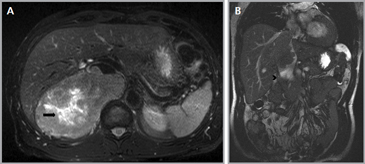

Figura 23. Carcinoma suprarrenal derecho. Corte axial de resonancia magnética ponderado en T2 con saturación grasa (a) en que se demuestra una masa suprarrenal derecha con áreas hiperintensas en su espesor probablemente determinadas por necrosis (flecha) y corte coronal en secuencia TRUFISP (b) en que se observa un trombo tumoral que expande el lumen de la vena cava inferior (cabeza de flecha).Puede también presentar invasión directa de otras estructuras vecinas, como riñón, páncreas, bazo y diafragma.